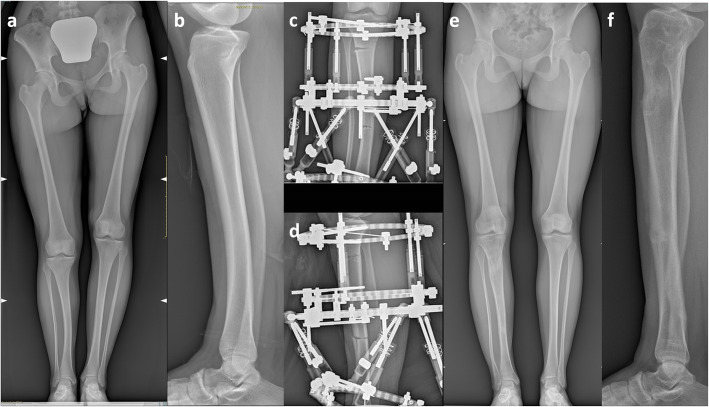

Fig. 5.

illustration showing the radiographs of a 14-years girl affected by CPMBT undergoing bifocal lengthening by circular hexapod external fixation device (TL-HEX Truelok Hexapod System® Orthofix srl - Verona – Italy) to equalize a LLD of 5 cm with a residual antero-posterior bowing of 8°. The deformity correction was achieved at the distal osteotomy with further lengthening at the proximal osteotomy.5a-b: pre-operative long-standing and lateral radiographs. 5c-d: early post-operative radiographs (antero-posterior and lateral view). 5e-f: postoperative long standing and lateral radiographs at the final follow-up one year after the external fixator removal

Twenty-two patients were treated at skeletal maturity (13.7 ± 1.8 years). The pre-operative radiographic data are summarized in Table 2. All these patients received leg lengthening by circular external fixation. We never bridged the ankle, but preferred foot splints attached to the fixator by elastic bands, in order to promote immediate full weight bearing and active rehabilitation of the ankle. Bifocal lengthening was accomplished in one case (Fig. 5), in which the deformity was corrected through the distal osteotomy, while lengthening was carried out at the proximal osteotomy, in order to reduce the time in frame, due to the better healing potential of the metaphyseal osteotomy. In this group, the final limb equalization was achieved in all patients, but we experienced 11 complications in 8 patients. According to Lascombes et al. [13], there were 2 grade IIa complications (2 operations to change or modify the frame) and 9 grade IIIa complications (1 delayed bone healing, 3 fibular nonunion, 1 knee joint stiffness; 2 achilles tendon shortening; 2 malalignment with residual anterior bowing of the tibia). Moreover the final LDTA was 83.3° ± 5.2° (range 72° - 90°), with 9 patients out of 14 showing a residual LDTA < 85°.